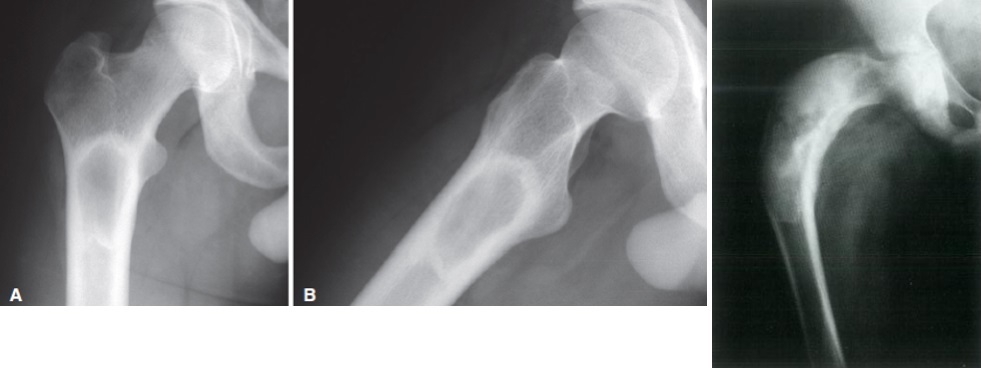

1

Q

Qual diagnóstico?

A

Lesão epifisária excêntrica

Fise aberta

dx: condroblastoma

2

Lesão na apófise